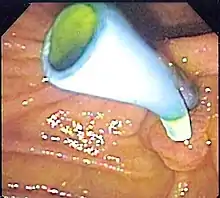

| Біліарні стенти забезпечують відведення жовчі з жовчного міхура, підшлункової та жовчних шляхів у дванадцятипалу кишку при таких станах, як висхідний холангіт через блокування каменем. | ![]() Ендоскопічне зображення біліарного стенту з боку ампули Фатера, зроблене під час дуоденоскопії |